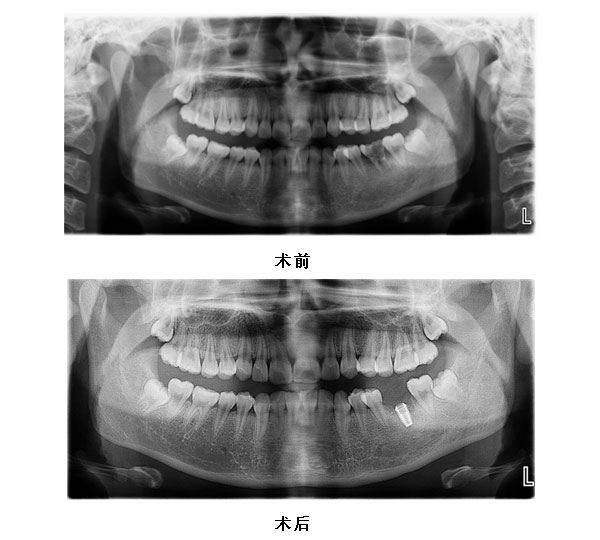

36拔除即刻种植义齿修复